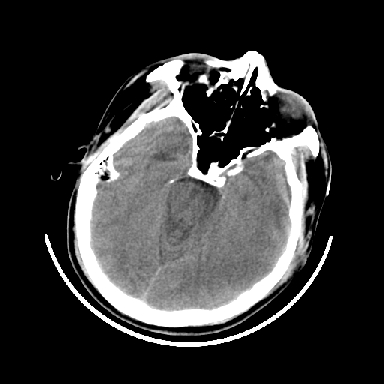

以下是引用dyqct在2007-4-9 11:18:00的发言:[br]左额颞顶叶、基底节区呈大片低密度区,累及皮质,中度占位效应,同侧侧脑室旁见小片状高密度区,边界清楚。中线结构向右弧形移位。右侧侧脑室略扩张。[br]考虑:1、左侧额颞顶叶、基底节区缺血性脑梗塞(符合大脑中动脉供血区)伴出血。[br] 2、建议增强扫描进一步检查。

以下是引用卜一在2007-4-9 15:08:00的发言:[br][br] 左侧额颞顶叶、基底节区缺血性脑梗塞(符合大脑中动脉供血区)伴出血。原因:多考虑外伤后出血,形成血栓所致。 [br]